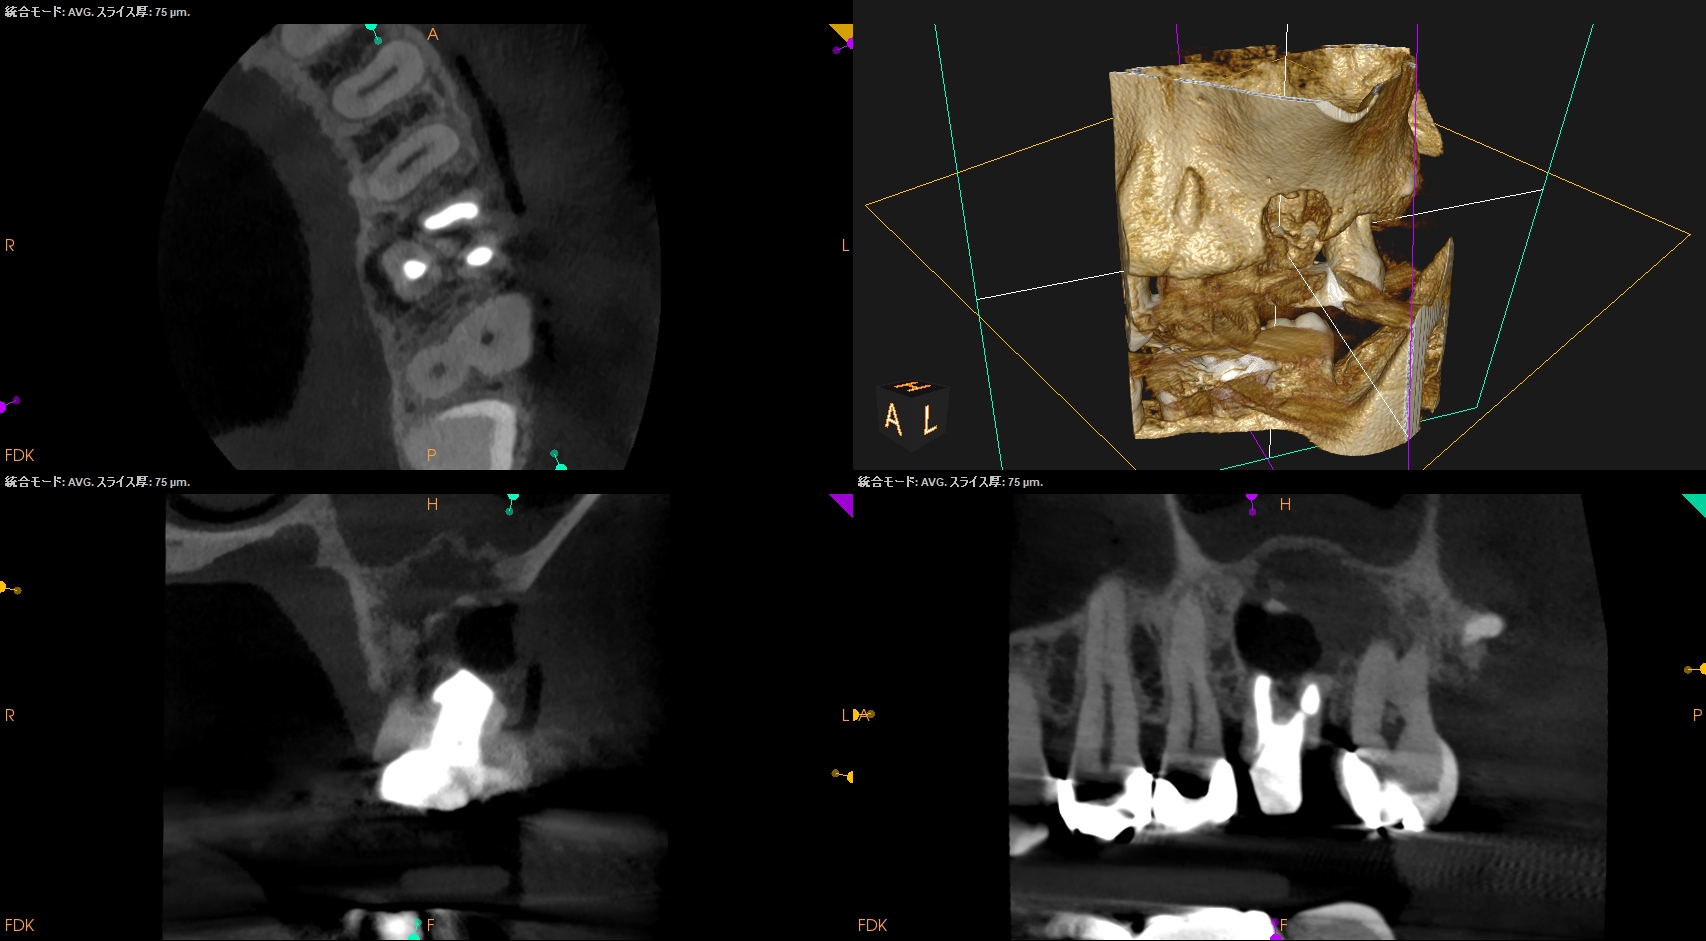

#14 Intentional Replantation 1yr recall(2025.6.6)

臨床症状は消えたが…

MB

DB

P

上顎洞炎は治癒し、Pの歯槽骨はかなり回復したがMB,DBは口腔内に歯根が出てしまっている。

つまりここがエンドポイントになるだろう。

このように

人為的に歯槽骨にダメージを与えて歯根を口腔内に露出させると頬側皮質骨は戻らずリセッションする

ことがわかる。

今後、こうした治療では気をつけないといけないだろう。

が、患者さんは臨床症状が消えたためこのまま最終修復となった。